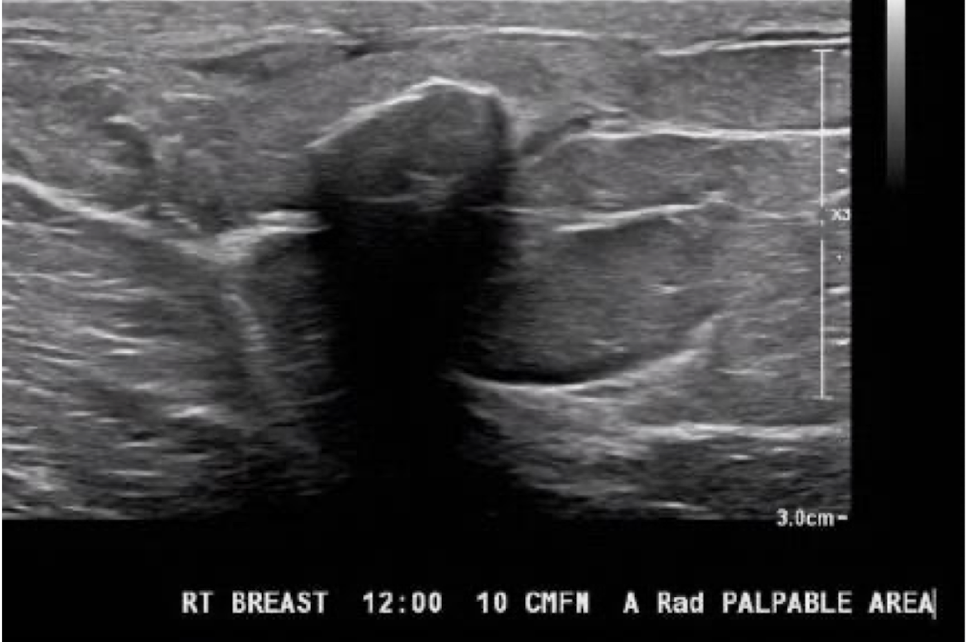

oil cyst

?